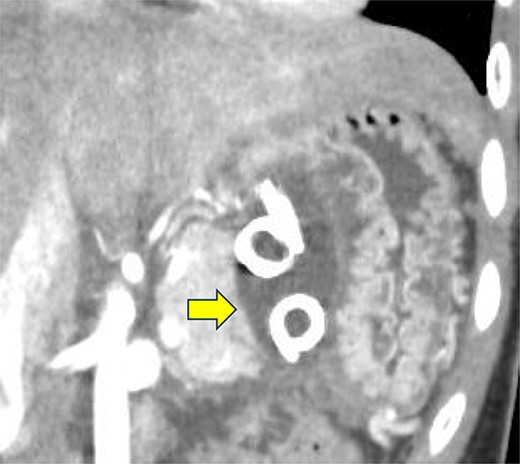

A 19-year-old woman who had fallen from a bicycle and bruised her upper left abdomen with handlebars presented to our emergency department 18 h after the injury with persistent abdominal pain. She was admitted with a diagnosis of pancreatic injury, as evidenced by elevated pancreatic amylase (P-Amy) levels (779 IU/L) and contrast-enhanced computed tomography (CT) showing a linear area with poor contrast in the pancreatic body (Fig. 1). Physical examination revealed a flat abdomen with mild tenderness in the upper left quadrant. Biochemical blood tests revealed elevated inflammatory markers; white blood cell count 10 950/μl, and C-reactive protein 0.58 mg/dl. On the fourth day, white blood cell count elevated to 21 940/μl and C-reactive protein elevated to 32.7 mg/dl. Contrast-enhanced CT revealed fluid accumulation, indicating pancreatic pseudocyst, primarily in the ventral pancreatic body and extending toward the spleen, along with edematous thickening of the adjacent stomach wall (Fig. 2).

Contrast-enhanced CT on admission. Linear areas with poor contrast in the pancreatic body and increased peripancreatic fatty tissue density were observed.